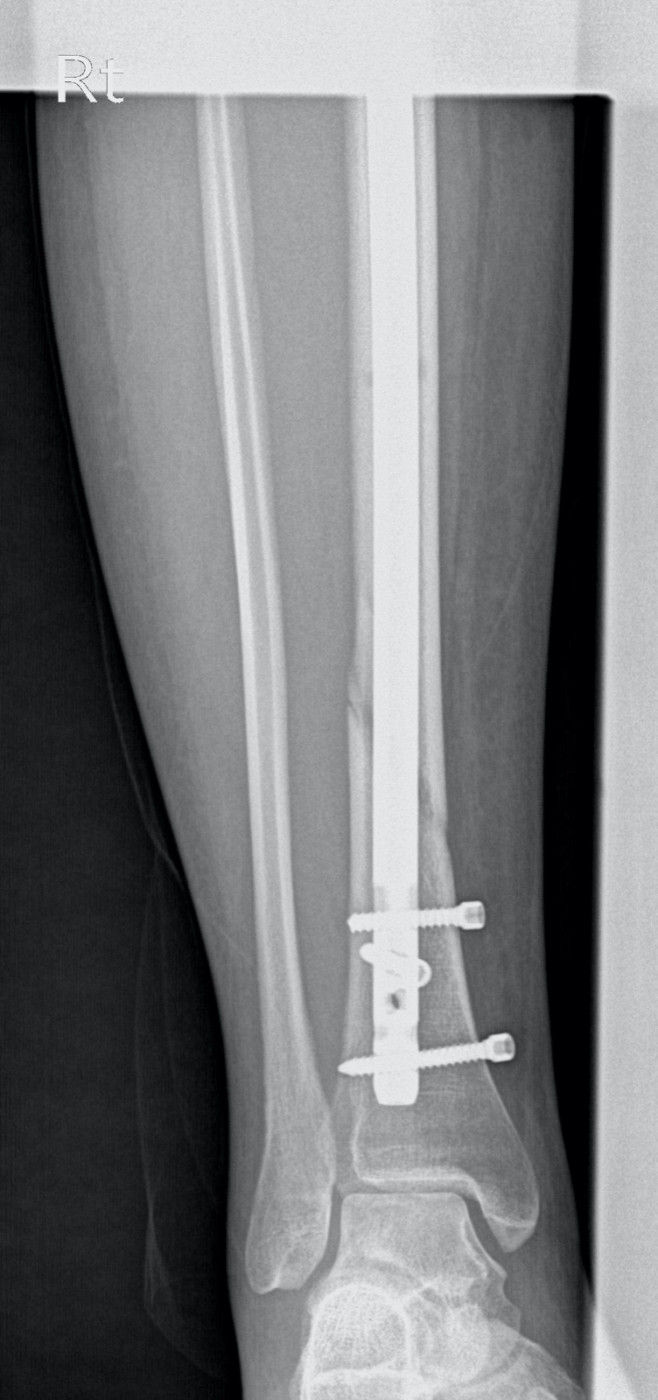

Перелом внутренней лодыжки у ребенка